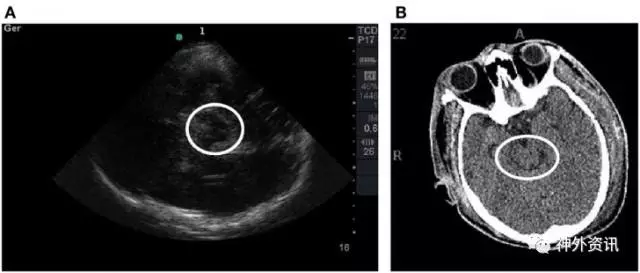

该研究共纳入15例患者,TCCS均在颅脑CT扫描前6h完成。比较患者进入ICU后的第1次CT扫描与TCCS结果。通过Bland-Altman法和评估组内相关系数(>0.75认为相关性强)分析二者一致性。15例患者中男性占80%,平均年龄为42±23岁,GCS评分为5。测量中线偏移,颅脑CT与TCCS结果的平均差异为0.30±2.1mm(组内相关系数:0.93,p<0.01)。第三脑室宽度测量,二者同样表现出极强相关性(0.88,p<0.01)。一致性分析显示,Bland-Altman法未表现出系统偏差。同时,与颅脑CT扫描相比,TCCS对判别非受压所致的中脑周围池和大脑外侧裂改变的精确度较高(图1、2)。

图1. A图中TCCS的白圈内中脑平面蝴蝶翼样结构,与B图中CT扫描结果相对应。